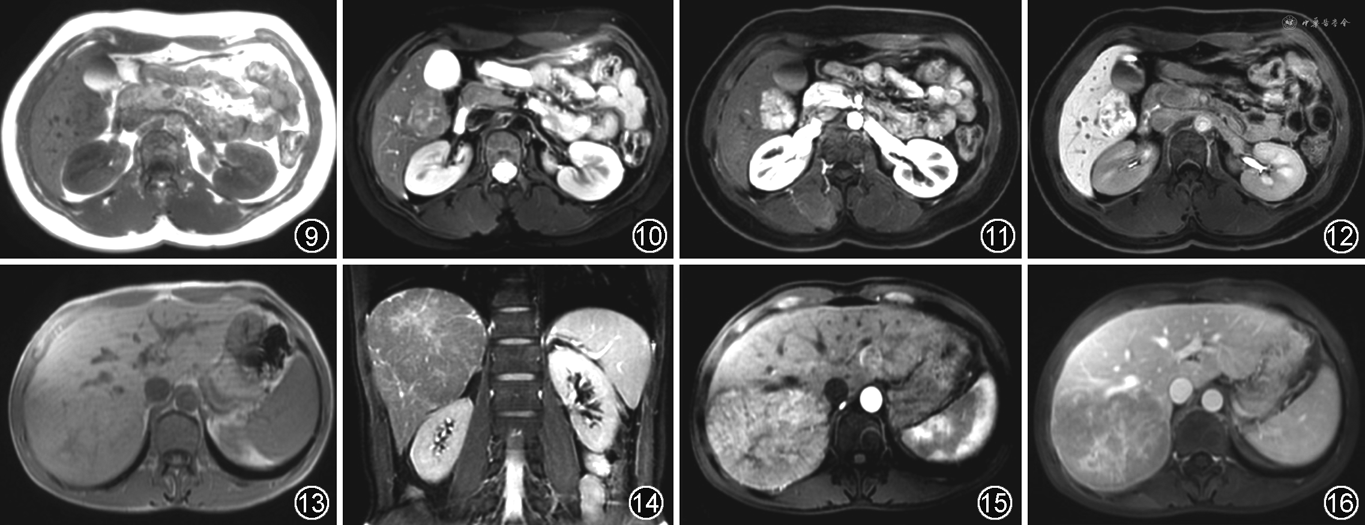

约20%的FNH影像表现不典型,肝胆细胞特异性对比剂增强扫描具有重要价值。FNH可以摄取肝胆细胞特异性对比剂,但因其内部胆管结构不与胆道交通,致对比剂排泄受阻,在肝胆细胞期呈等或高信号,尤其是环形高信号更具特异性,中心瘢痕在各期均无强化,呈低信号(图9~12)。

MRI上,T1WI为等或低信号,T1WI反相位上无信号减低,T2WI呈不均匀高信号。70%的病灶内可见中央瘢痕,在T2WI呈高信号,且伴有延迟强化,酷似FNH或高分化肝细胞癌。增强动脉期明显强化,门静脉期和延迟期持续强化。在肝胆细胞期大部分呈低信号(图13~16)。